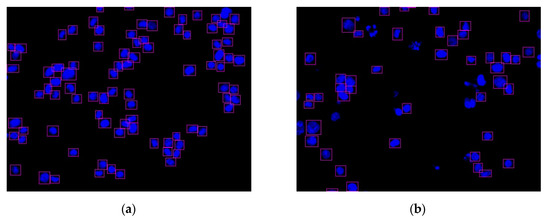

Figure 12.

Two nucleus images recognized by the YOLO algorithm: (a) HCT116 cell with DMSO (no.4484); (b) HCT116 cell with dinaciclib (no.4496).